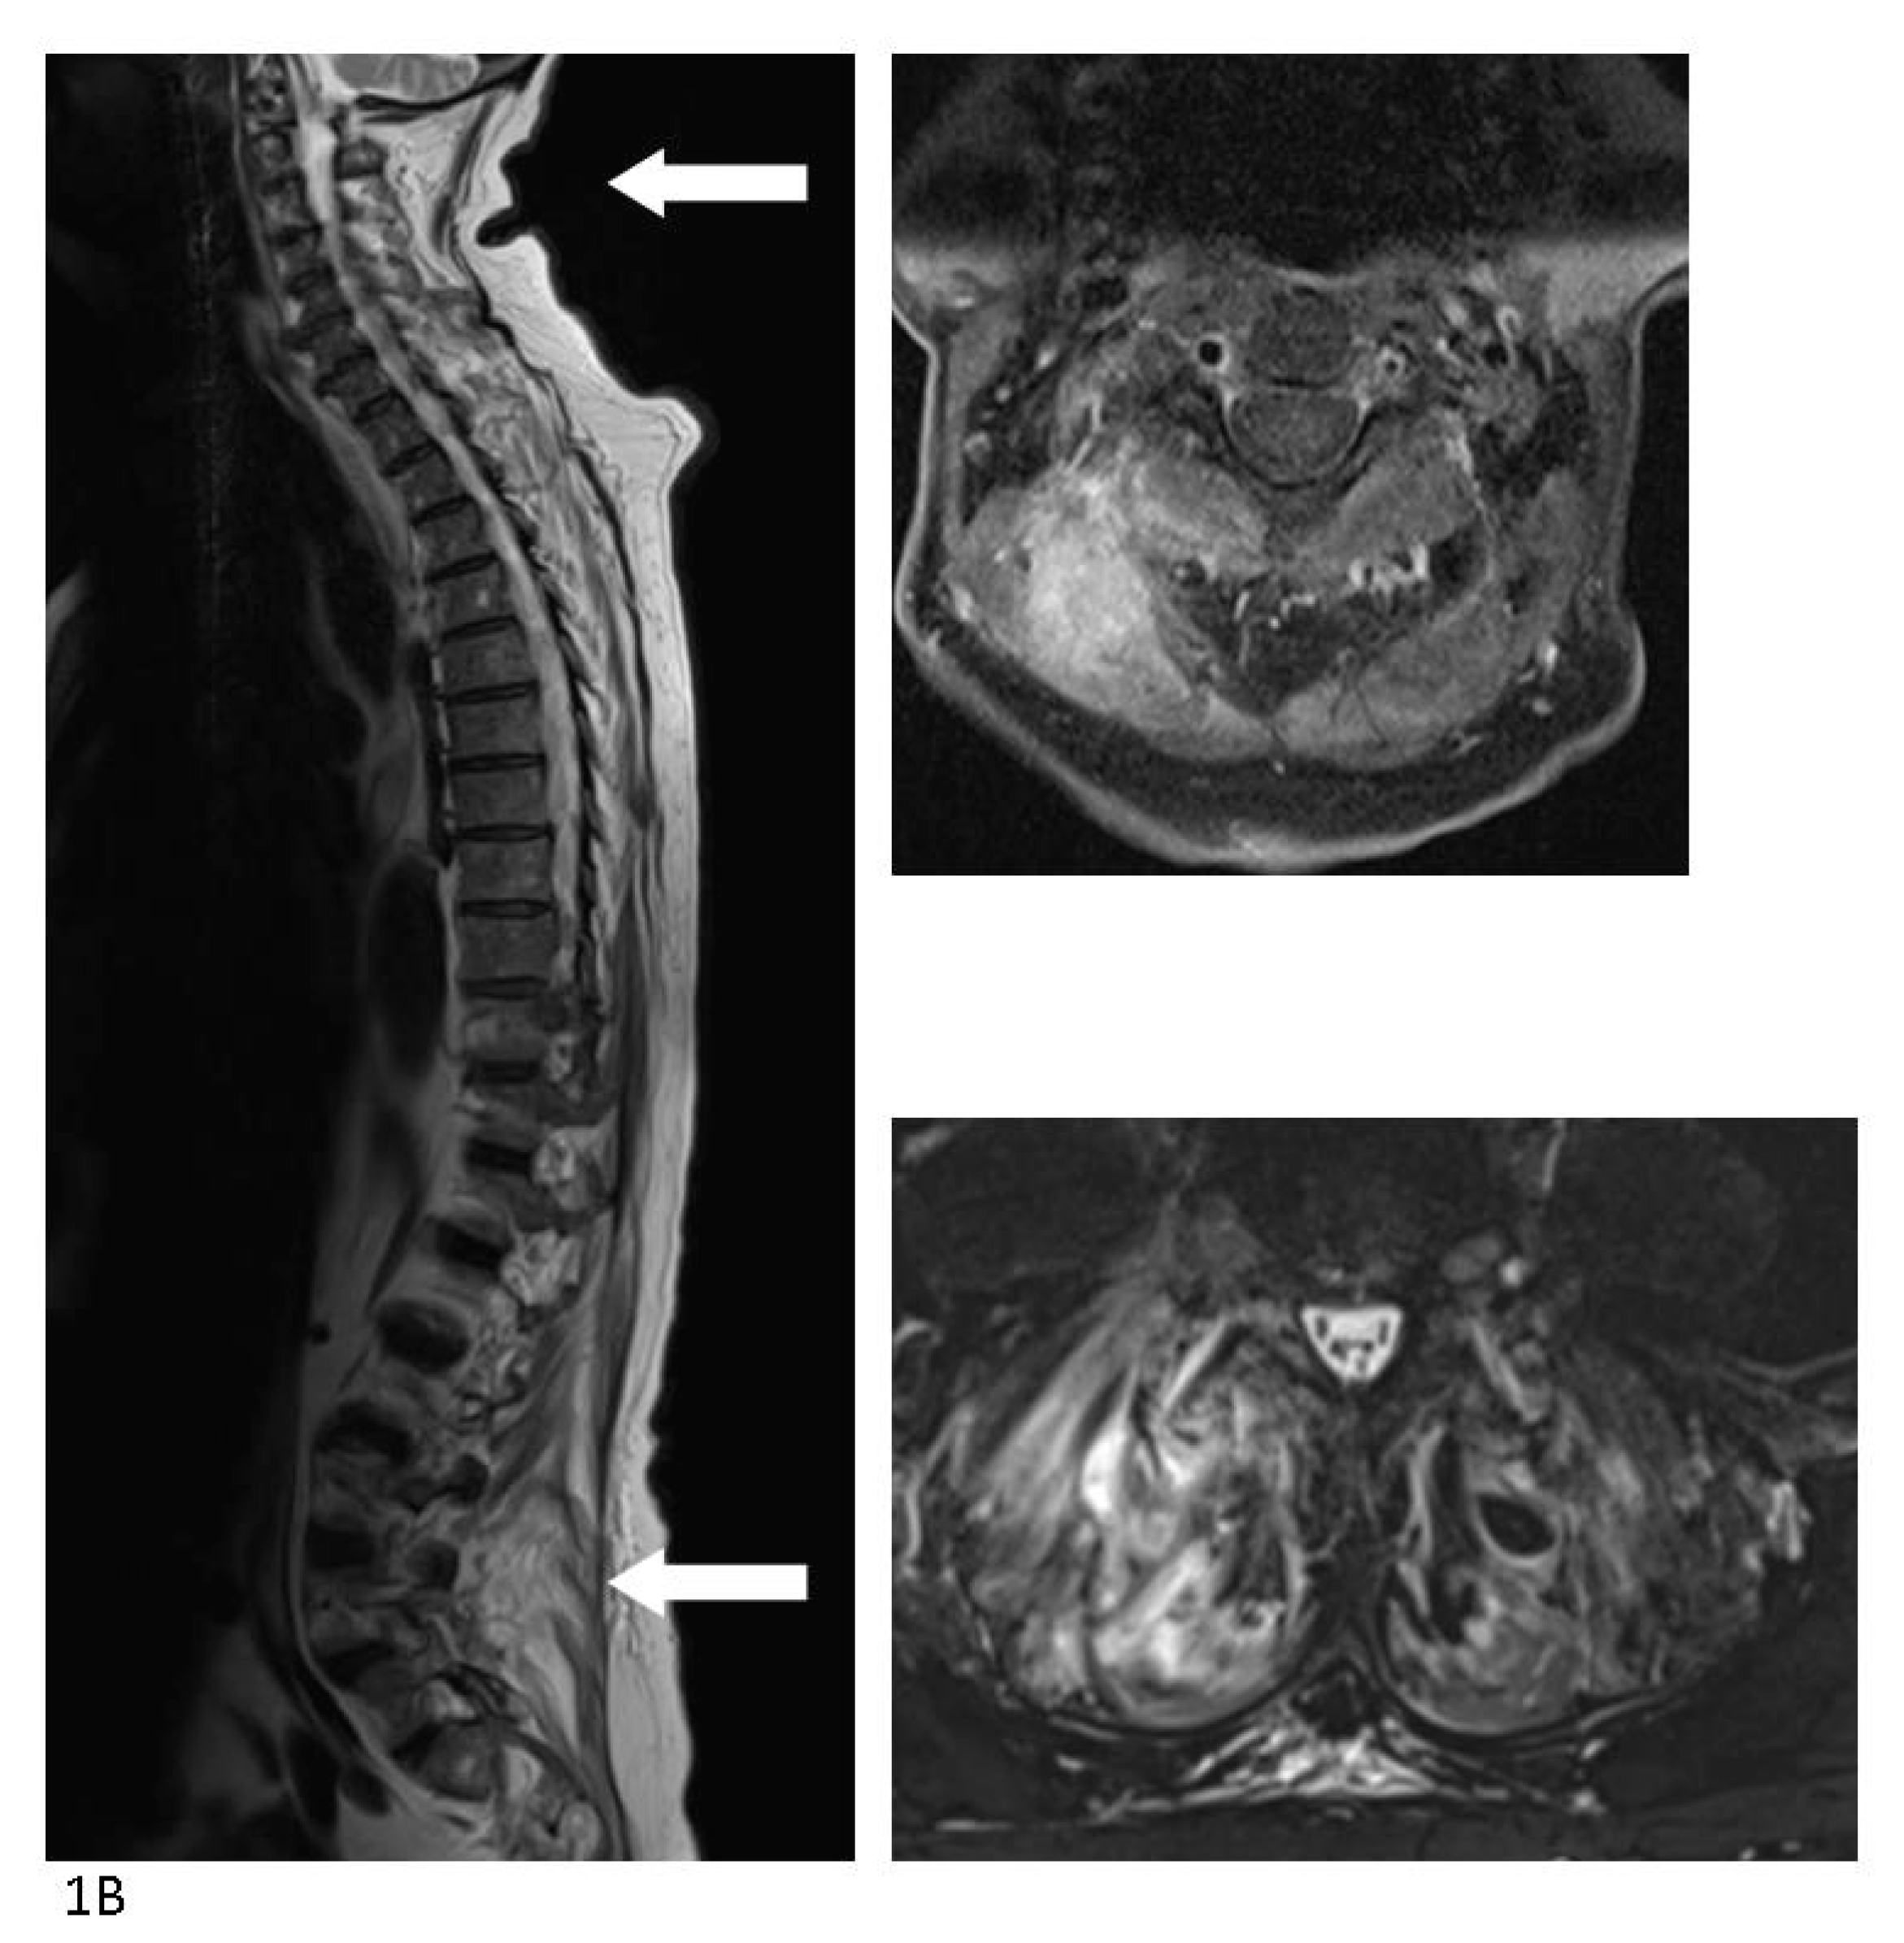

Staphylococcus aureus Bacteremia from Diffuse Muscular Infection Following Acupuncture Visualized by 18F-FDG PET/CT and MRI